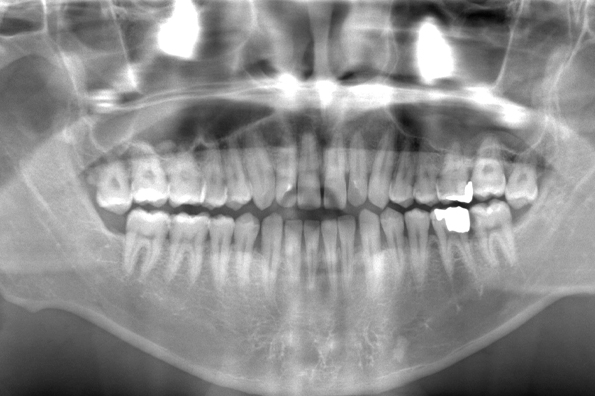

CASE 10

| 年齢・性別 | 39歳・男性 |

| 主訴 | 左上下親知らず抜きたい |

| 抜歯期間 | 30分 |

| 抜歯費用 | 約2,500円(保険内) 別途CT撮影で3,000円 (2022年7月現在) |

| 抜歯内容 | 左上下の親知らず抜歯 |

| 治療方針 |

親知らずは抜いたほうが良い認識はあったものの、痛みや腫れが出ることを知って、勇気が出ないままでいたとのことでした。 そのまま放置していたら虫歯になってしまい、今回ご来院されました。しっかりと麻酔をして緊張をほぐしながら抜歯を始めました。完全萌出のため、時間を要することなくすぐに抜歯することができました。 |